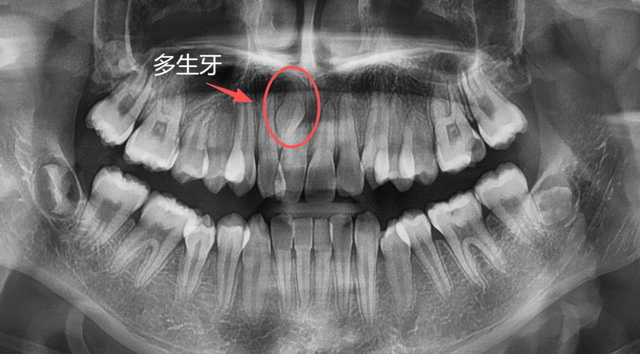

长在上颌窦、鼻腔方向的异位牙,长在牙槽骨深处的多生牙,常常埋伏于骨内,需要骨开窗才能拔除,具有一定的难度。

牙根的形态、数量是天生的,无法后天干预,但是对于部分异位牙、埋伏牙,我们可以在小朋友替牙期的这个阶段通过相应的医学手段来干预,避免一些成年后的拔牙。

儿童上颌多生牙

建议家长在小朋友处于替牙期的时候,不管有没有牙疼,都找专业的口腔医生进行检查,必要时拍片看一下牙胚的数量有无出入,关注一下牙齿是否按正常的顺序完成了替换,如有异常情况,可以及时干预。